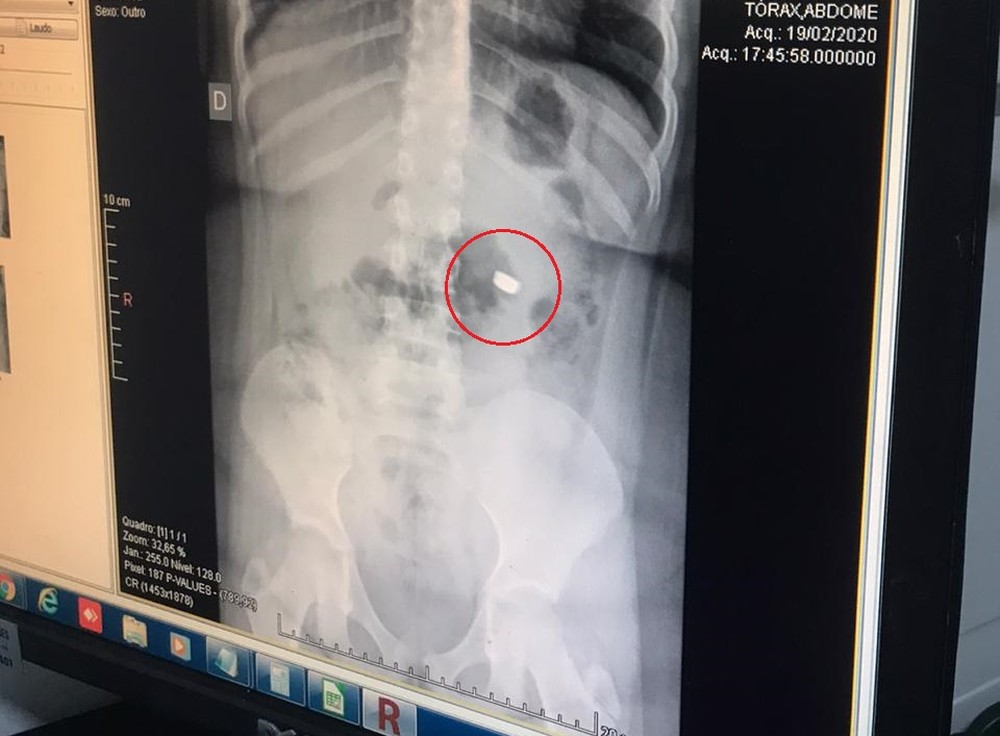

A menina fez pelo menos quatro exames de raio-x para acompanhar o trajeto da bateria no sistema digestivo. Apesar do susto, a criança passa bem.